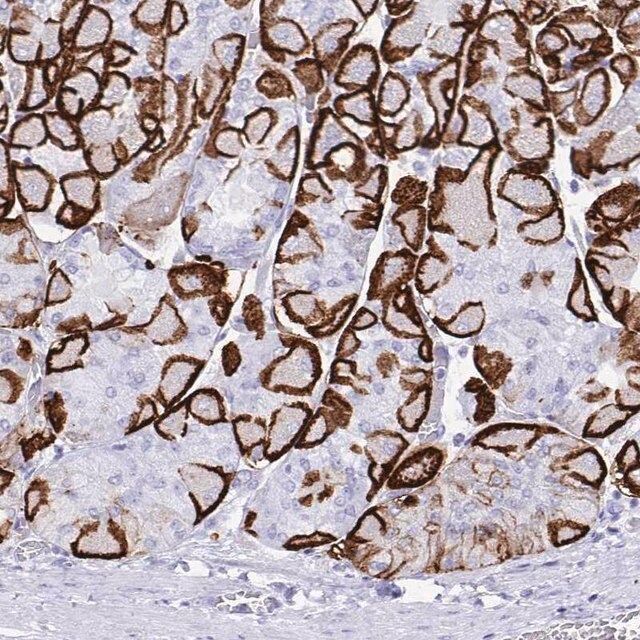

水通道蛋白 4 (aquaporin 4,AQP4) 是一种内源性蛋白,属于水通道蛋白家族,由 13 个成员组成。该基因位于人类 18 号染色体 q11-q12,有 4 个外显子和 3 个内含子。编码的蛋白有 5 个环,由 6 个跨膜结构域干预。环 A、C 和 E 面向浆外区,环 B 和 D 存在于胞浆区。在肺、胃和肾等外周器官中表达。是中枢神经系统表达的主要水通道。它由星形胶质细胞表达,并优先定位于星形胶质细胞的终足突起。它以两种可变剪接形式存在— 长的称为 M1,短的称为 M23。

人类蛋白质图谱项目可细分为三个方面的工作:人类组织图谱、癌症图谱和人类细胞图谱。支持 Tissue and Cancer Atlas 项目而产生的抗体,已经通过免疫组化针对数百个正常和疾病组织进行了测试,通过 Human Cell Atlas 项目最近的努力,很多已经通过免疫荧光法进行了表征,不仅在组织级别,现在也在亚细胞级别绘制了人类蛋白质组图谱。通过点击图像库链接,可以在 Human Protein Atlas (HPA) 位点上查看这些图像和这个庞大数据集的集合。要查看这些协议 和其他有关 Prestige 抗体和 HPA 的有用信息,请访问sigma.com/prestige。

水通道蛋白 4 (aquaporin 4,AQP4) 是脑内主要的水转运体,被认为是维持脑内水分稳态的重要物质。因此,AQP4 可能在脑水肿的发病机制中起重要角色。研究显示,这种转运体在脑缺血中过度表达。因此,它可能有潜力成为缺血性脑水肿的治疗靶点。该基因多态性与脑损伤反应和脑外伤患者的临床预后相关。AQP4 的短亚型 (M23) 有利于颗粒正交排列 (orthogonal array of particles,OAP) 的形成,OAP 的大小由短 (M23):长 (M1) 亚型的比例决定。已知这些 OAP 与视神经脊髓炎 (NMO) 中产生的致病性自身抗体相互作用。因此,对该蛋白的进一步研究可能为 NMO 的发病机制和治疗提供见解。

- 44例正常人类组织以及20例最常见癌症类型组织的IHC组织阵列。